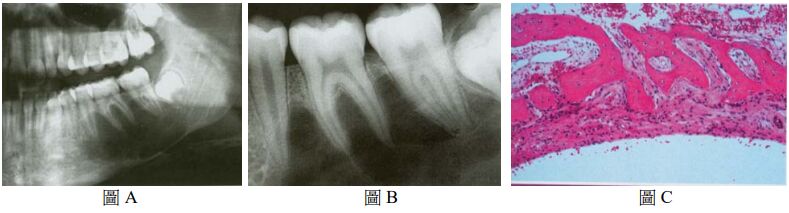

76.一位 16 歲男孩在常規 X 光檢查時,發現左下顎臼齒下方有一放射線透性影像,牙根之間呈現扇形(scalloped),病灶下緣周界較不清晰(圖 A),根尖片可見到清晰之齒槽骨板(lamina dura)(圖 B),患處牙齒之牙髓均呈活性反應,口外醫師安排活體切片檢查時發現放射線透性病灶內空無一物,刮取病灶周邊組織鏡檢(圖 C),可見鄰近之骨組織有一薄層含血管之結締組織,並沒有發現任何上皮襯底(epithelial lining)。您認為下列何者較符合上述之診斷? (A) 動脈瘤性骨囊腫(aneurysmal bone cyst) (B) 史塔尼氏囊腫(Stafne bone cyst) (C) 單純性骨囊腫(simple bone cyst) (D) 齒源性角化囊腫(odontogenic keratocyst)